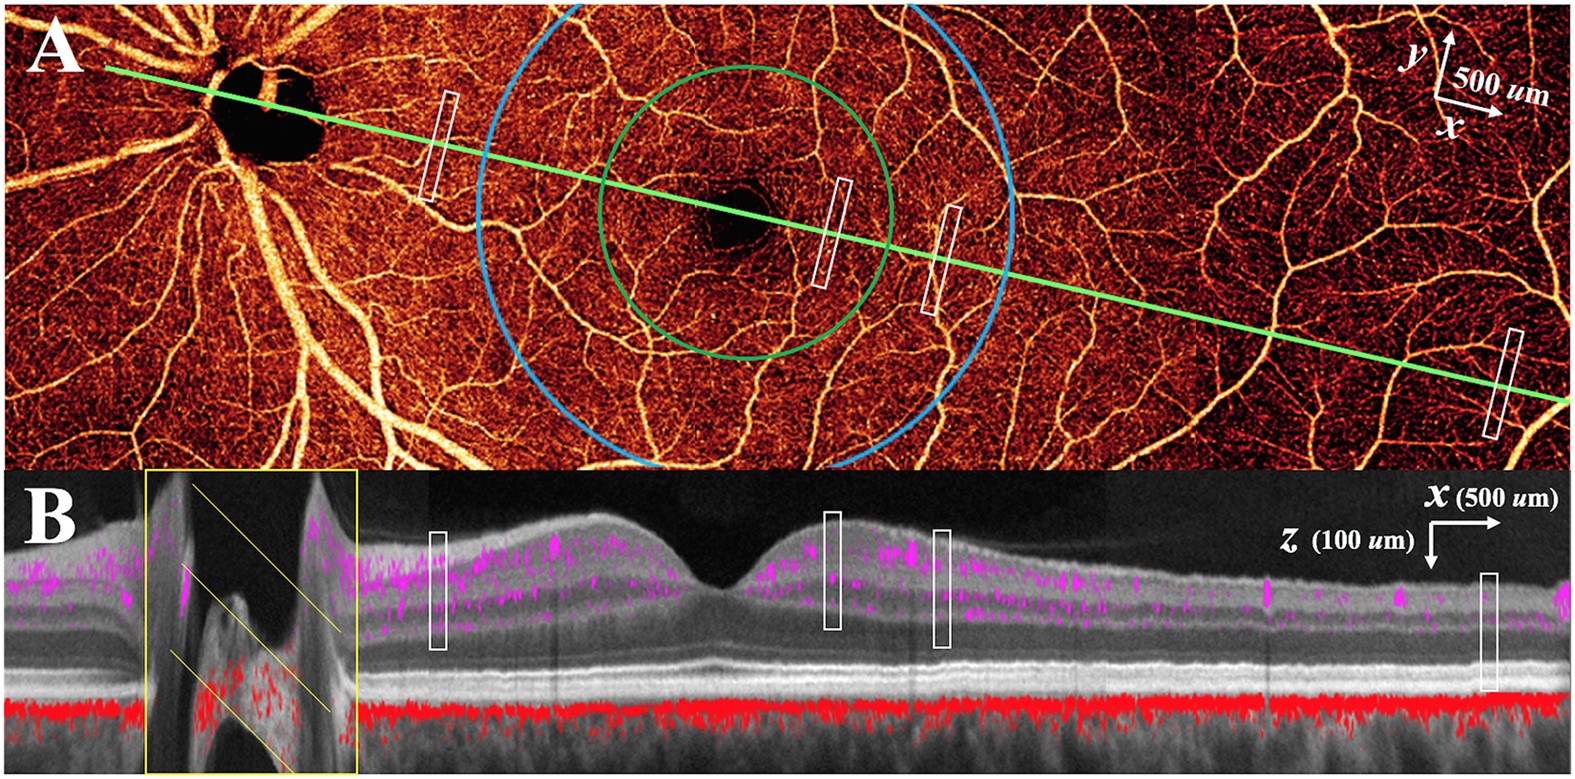

Figure 2: Projection-resolved optical coherence tomography angiography (PR-OCTA) in the left eye of a normal study participant.

Four 4.5 × 4.5 mm OCTA volumes were montaged. (A) 14.2 × 4.5 mm en face OCTA of the inner retina. The cross-sectional image (B) is taken along the maculopapillary axis (green line joining the centers of the fovea and optic disc). (B) Color-composite cross-sectional OCTA (14.2 × 0.7 mm) showing retinal (purple) and choroidal (red) blood flow superimposed on gray scale reflectance image of static structures. The white rectangles in (A) and (B) represent the 0.1 × 0.8 × 0.25 mm (x × y × z) sampling regions at locations in the peripapillary, parafoveal (green circle), perifoveal (blue circle), and peripheral (7 mm temporal to fovea) retina for capillary density measurements.